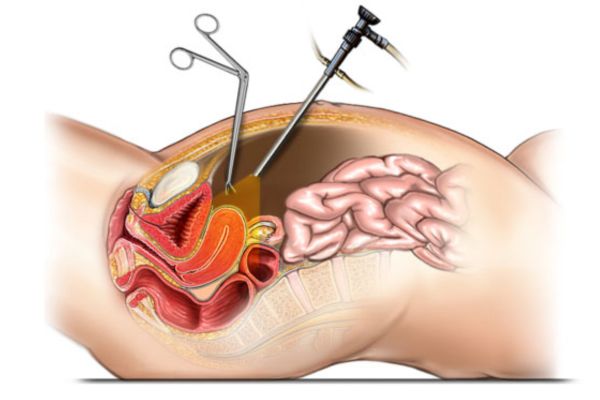

Minimally invasive procedures for ovarian cysts, fibroids, endometriosis & hysterectomy.